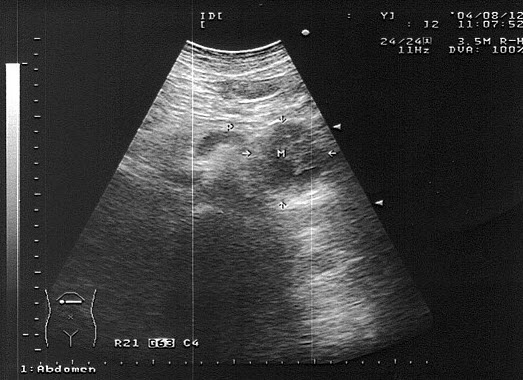

9、单项选择题

女,51岁,纳差、消瘦。结合超声声像图,诊断为()

A.胰腺癌